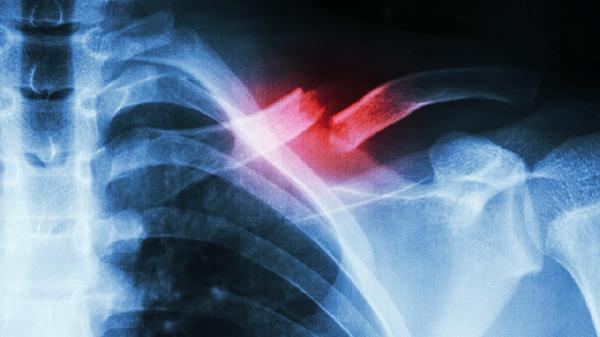

二、影像学检查

影像学检查有助于排除其他胸壁疾病并明确肋软骨炎程度。X线检查可显示肋软骨钙化情况,但早期病变可能无异常表现。超声检查能清晰显示肋软骨肿胀、增厚等炎症改变,具有无创、可重复的优势。CT检查可三维重建肋软骨结构,对复杂病例诊断价值较高。磁共振成像能更敏感地发现早期炎症改变。